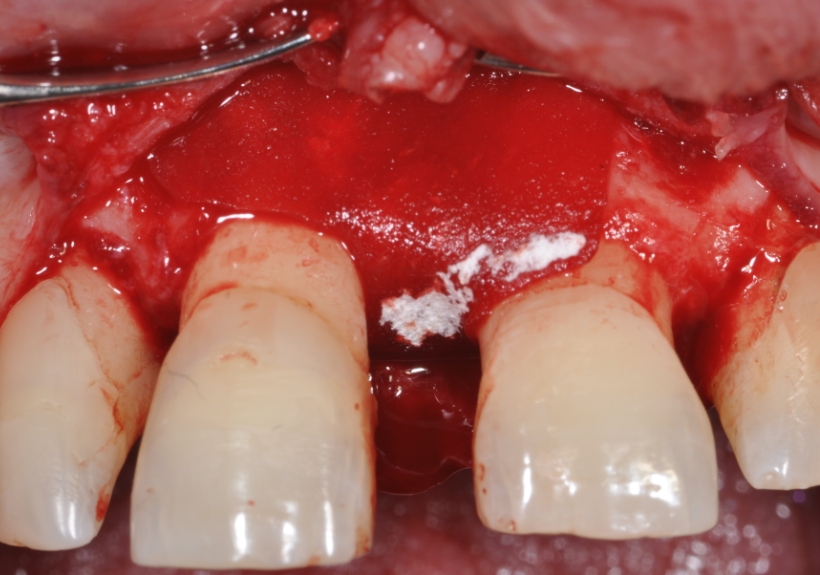

Immediate implant placement in the maxilla with contour GBR - Dr. K. Loukas

The patient presented with a terminal fracture of the crown tooth number 12